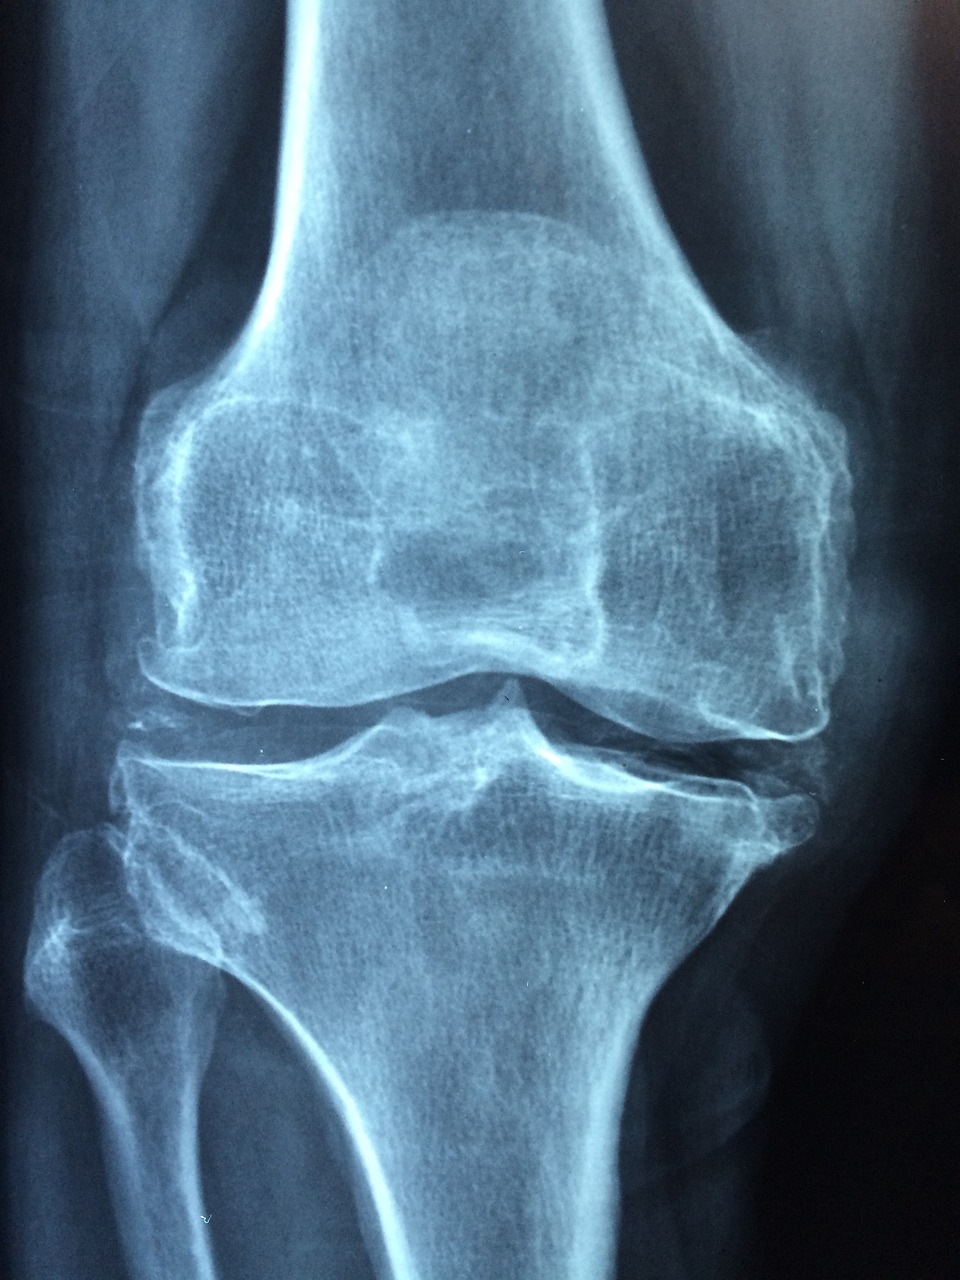

퇴행성 관절염일 경우

퇴행성 관절염은 말 그대로 노화로 인해 생기는 병으로 뼈의 관절면을 감싸고 있는 관절의 연골이 마모되어 생기는 병입니다. 관절 주변에 활액막에 염증이 생기고 이 염증이 치료되지않을 경우 통증이 심해지면서 물이 차기도 합니다.

이럴 경우 체중을 줄이고 근육량을 늘려주는 운동이 필요합니다.